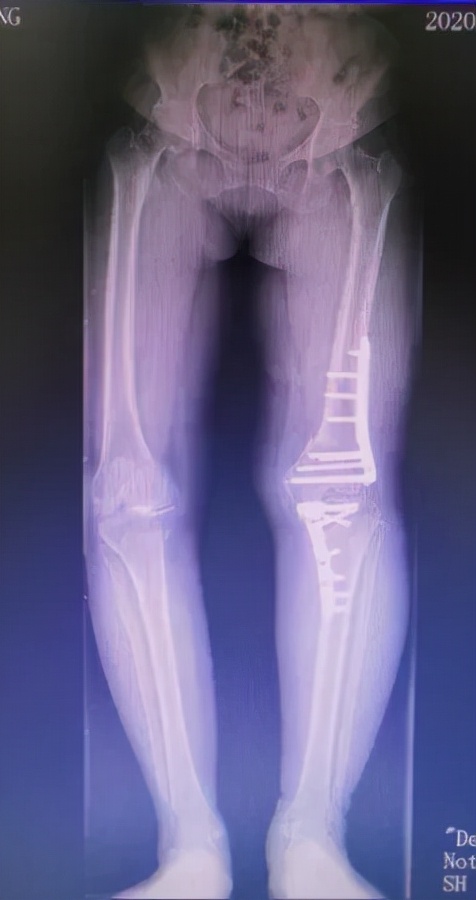

入院后刘万军主任对赵女士进行了详细的检查发现,赵女士的左膝关节存在严重的内翻畸形,关节间隙明显缩小。不仅股骨侧存在畸形,且胫骨侧也存在畸形。当股骨和胫骨均存在畸形时,试图仅通过胫骨侧截骨或股骨侧截骨来矫正这类畸形可能会导致术后关节线发生非生理性倾斜,使得关节表面软骨遭受的剪切力增加。长期的剪切应力会使得软骨超过其承载负荷的极限,造成软骨面的损伤,加快骨关节炎的发生和进展。此外,关节线倾斜还可能引起膝关节周围韧带的松弛,从而在负重时容易产生半脱位。因此,刘万军主任团队准备对赵女士的左膝关节同时进行股骨远端截骨术+胫骨高位截骨术(DFO+HTO),以此矫正左膝严重内翻畸形,更好地恢复关节力线和膝关节的正常解剖角度。

通过术前在计算机上精确规划截骨线及矫正角度后,刘万军主任团队对赵女士的左膝同时进行了股骨远端截骨术+胫骨高位截骨术。先取左膝关节的正中切口,行内松解后,按标准手术行髌骨修整。股骨切骨完整后,试装假体复位,调试后用骨水密固定安装假体。之后取左膝关节屈膝90度,采用外侧倒T行切口,分离胫骨外侧组织,在胫骨平台远侧2cm处截骨,用C形臂X线机检查位置,反复检查下肢对线,在腓骨前方行内固定。手术进行的非常顺利,出血少,历时约3小时10分钟。术后赵女士的膝关节疼痛消失,膝内翻畸形得到明显改善。

术后半年